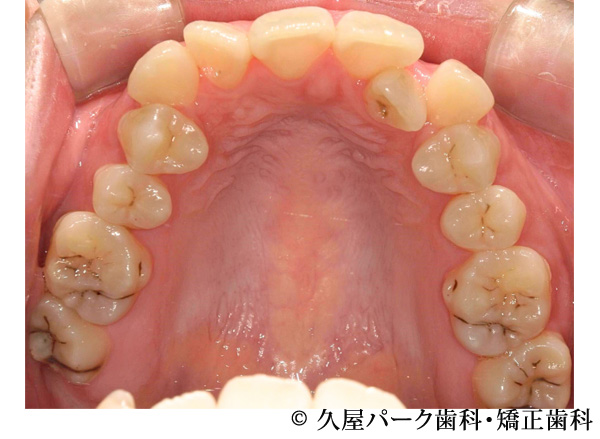

【症例3】叢生(歯のでこぼこ)の症例

- 治療前

- 治療後

- 治療名

- 叢生(歯のでこぼこ)の症例

- 費用

- 660,000円(税込)

※矯正相談・精密検査・オーダーメイド治療計画の費用はいただいておりません - 期間

- 2年4ヵ月

- 通院

- 1ヵ月ごと

- 性別・年代

- 女性・20代

治療内容

患者様の症状

全体的にでこぼこが気になるということで当院で治療を開始された患者様です。

治療法

ワイヤー矯正での歯並び改善

上下左右4番抜歯 -

治療結果

でこぼこが改善されました。

※治療結果は個人差があります。

治療を行う上での注意点(リスク・副作用)

・治療の初期段階では、痛みや不快感が生じやすくなりますが、一週間前後で慣れます

・歯の動き方には個人差があるため、予想された治療期間より延長する場合があります